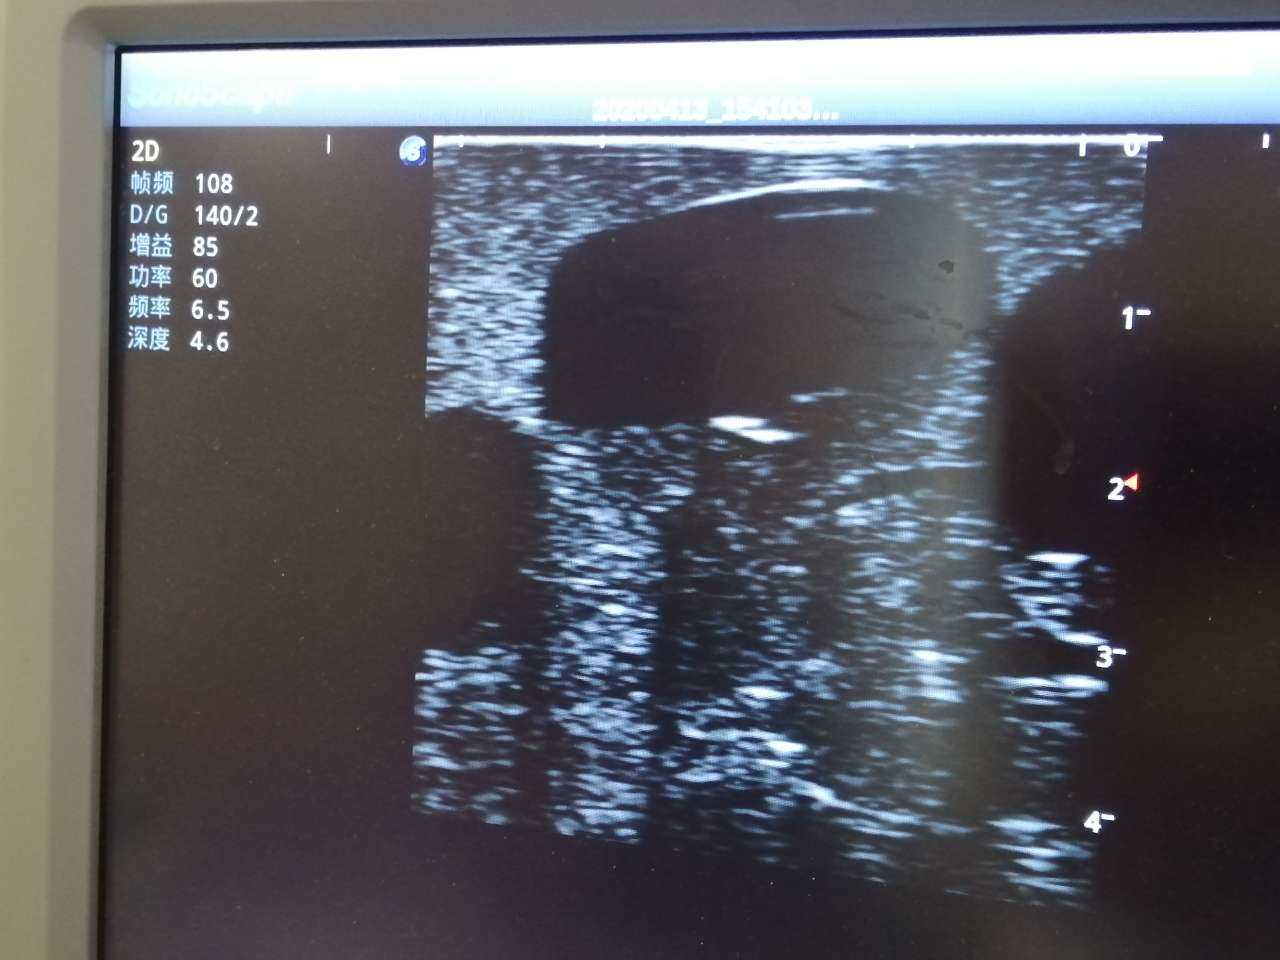

· High-quality ultrasound images to show skin, soft tissues, abscess cavity and pus

· Ultrasound recognition of abscess

· Different abscess types: single sac on the right side and multiple sacs on the left side